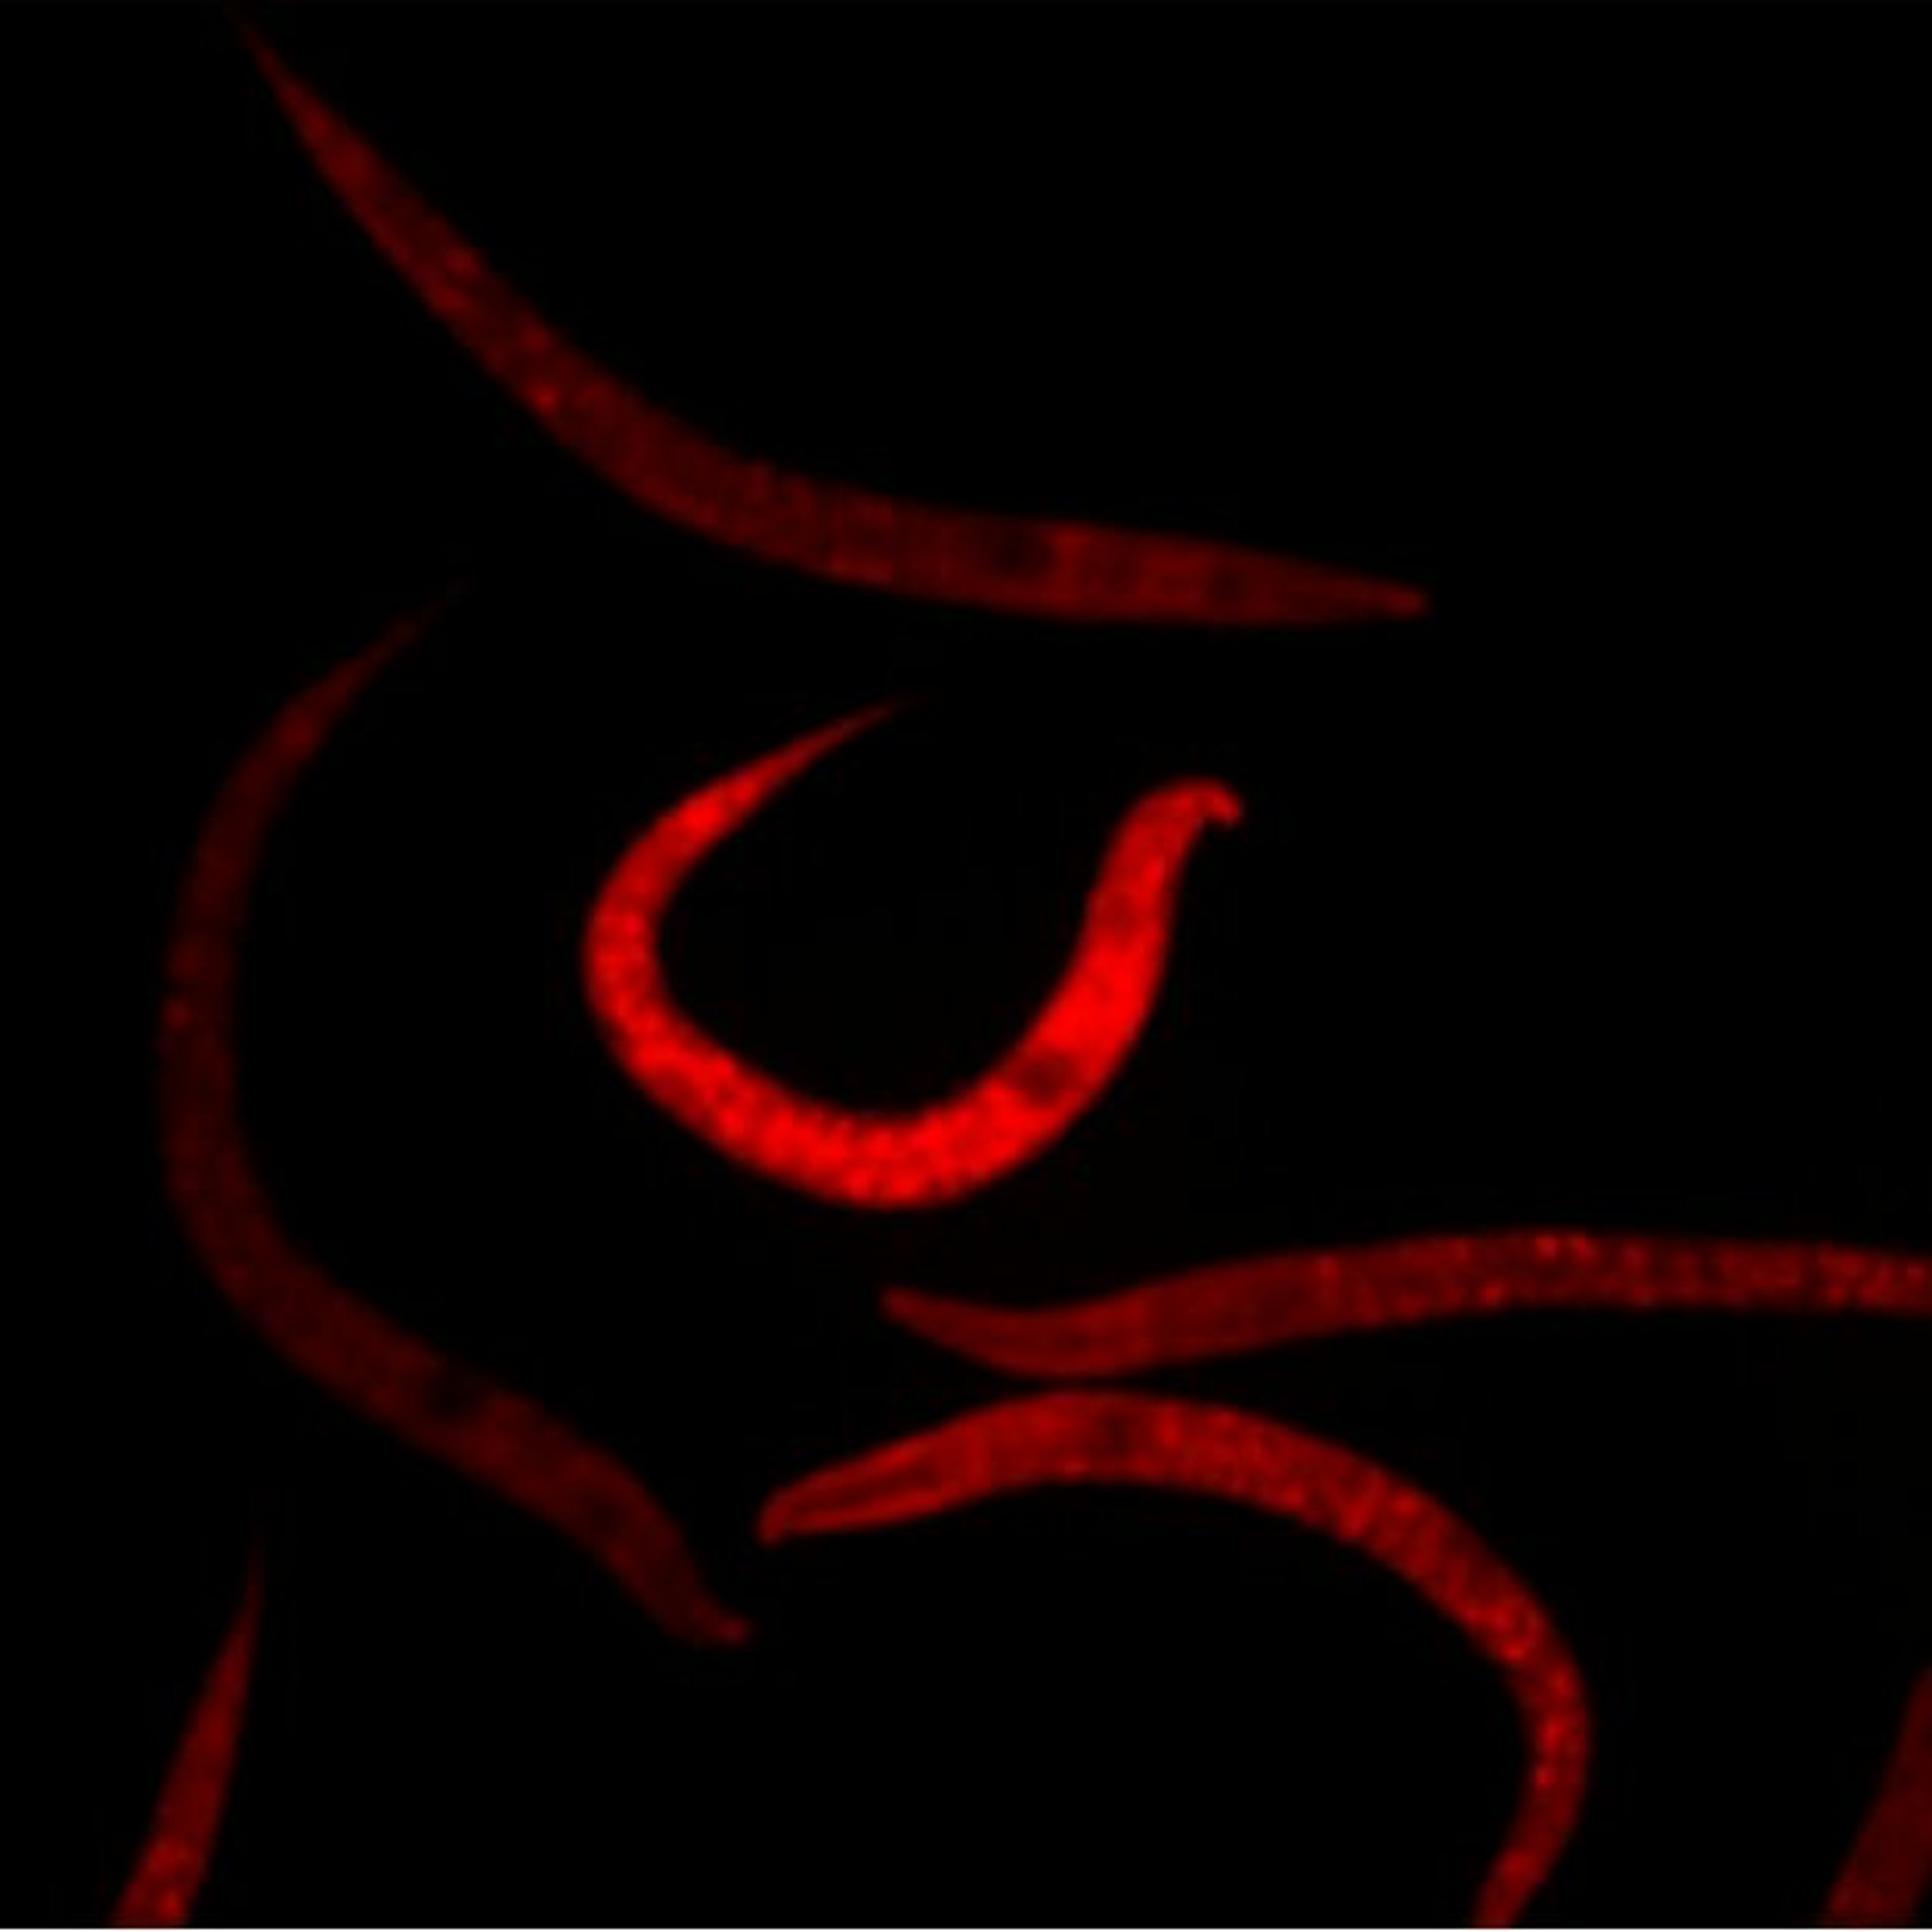

Previous studies have demonstrated an association between tau levels and mitochondrial metabolism, however, determining which one proceeds the other has yet to be fully illuminated. Shedding light on this subject, researchers—from the University of Copenhagen, National and Kapodistrian University of Athens and the National Institutes of Health’s National Institute on Aging—used a Caenorhabditis elegans (C. elegans; roundworm/nematode) model of tau to examine mitochondrial changes over time. Their paper was chosen as the cover of Aging (Aging-US) Volume 13, Issue 21, published in November of 2021 and entitled, “Alteration of mitochondrial homeostasis is an early event in a C. elegans model of human tauopathy”.